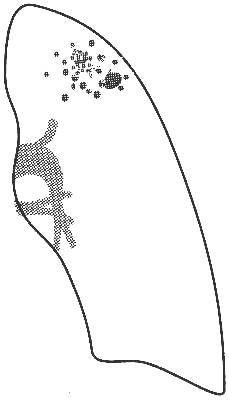

Рис. 4 Рентгенограмма ОГК и схема к ней левого легкого. В апикальном отделе S1–2 левого легкого определяется обогащенный легочный рисунок за счет множественных полиморфных преимущественно среднеочаговых теней, склонных к слиянию с нечеткими контурами; здесь же имеются плевроапикальные наслоения. Корни легких структурны, не расширены. Купол диафрагмы четкий, синусы свободны. Заключение: Очаговый туберкулез в S1–2 левого легкого в стадии инфильтрации. Список использованной литературы: 1. Помельцов К.В. Рентгенологическая диагностика туберкулеза легких. М.:Медицина, 1971. 367 с. 2. Рубинштейн Г.Р. Туберкулез легких. М., 1948. 228 с. 3. Струков А.И., Соловьева И.Л. Морфология туберкулеза в современных условиях. М.: Медицина, 1986. 228 с. 4. Ерохин В.В., Земскова З.С., Уварова О.А. и др. Патологоанатомическая диагностика прогрессирующих форм туберкулеза легких в связи с новой клинической классификацией // Пробл. туб. 1996. №4. С. 32–37. 5. Авербах М.М. Туберкуломы легкого. Клинико-анатомический анализ, патологическая анатомия, патогенез и классификация по материалам резекций. М.:Медицина, 1969. 336 с. 6. Александрова А.В. Рентгенологическая диагностика туберкулеза органов дыхания. М.:Медицина, 1983. КУРСКИЙ ГОСУДАРСТВЕННЫЙ МЕДИЦИНСКИЙ УНИВЕРСИТЕТ Кафедра лучевой диагностики Зав. кафедрой, д.м.н., профессор Губарев Е.А.